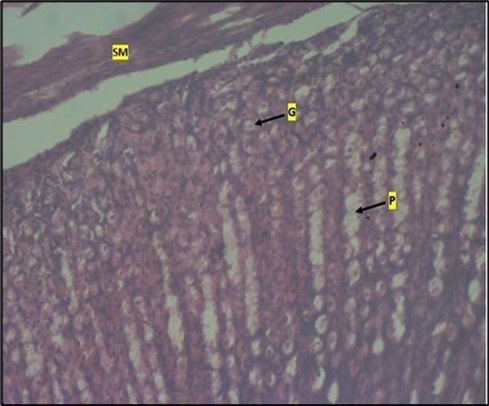

Histological examination of the stomach in control animals showed normal appearance of epithelial cells lining the mucosa and normal smooth muscles in the submucosa (Figure 8). However, administration of Abelmoschus esculentus at low dose showed deep epithelial gastric area with marked depletion of pits and goblet cells (circled area) and normal smooth muscles in the submucosa (Figure 9) and the high dose group showed dysplasia of gastric pits with goblet cells in the mucosa and the smooth muscles in the submucosa were mildly eroded (Figure 10).

Figure 10.Image of a wistar rats stomach treated with high dose of abelmoschus esculentus showing dysplasia of gastric pits with the arrows mark (p). Goblet cells mark with arrow (g) appear at the basal mucosa and smooth muscle (sm) appear mildly eroded. The slide was stained using h & e technique. X100